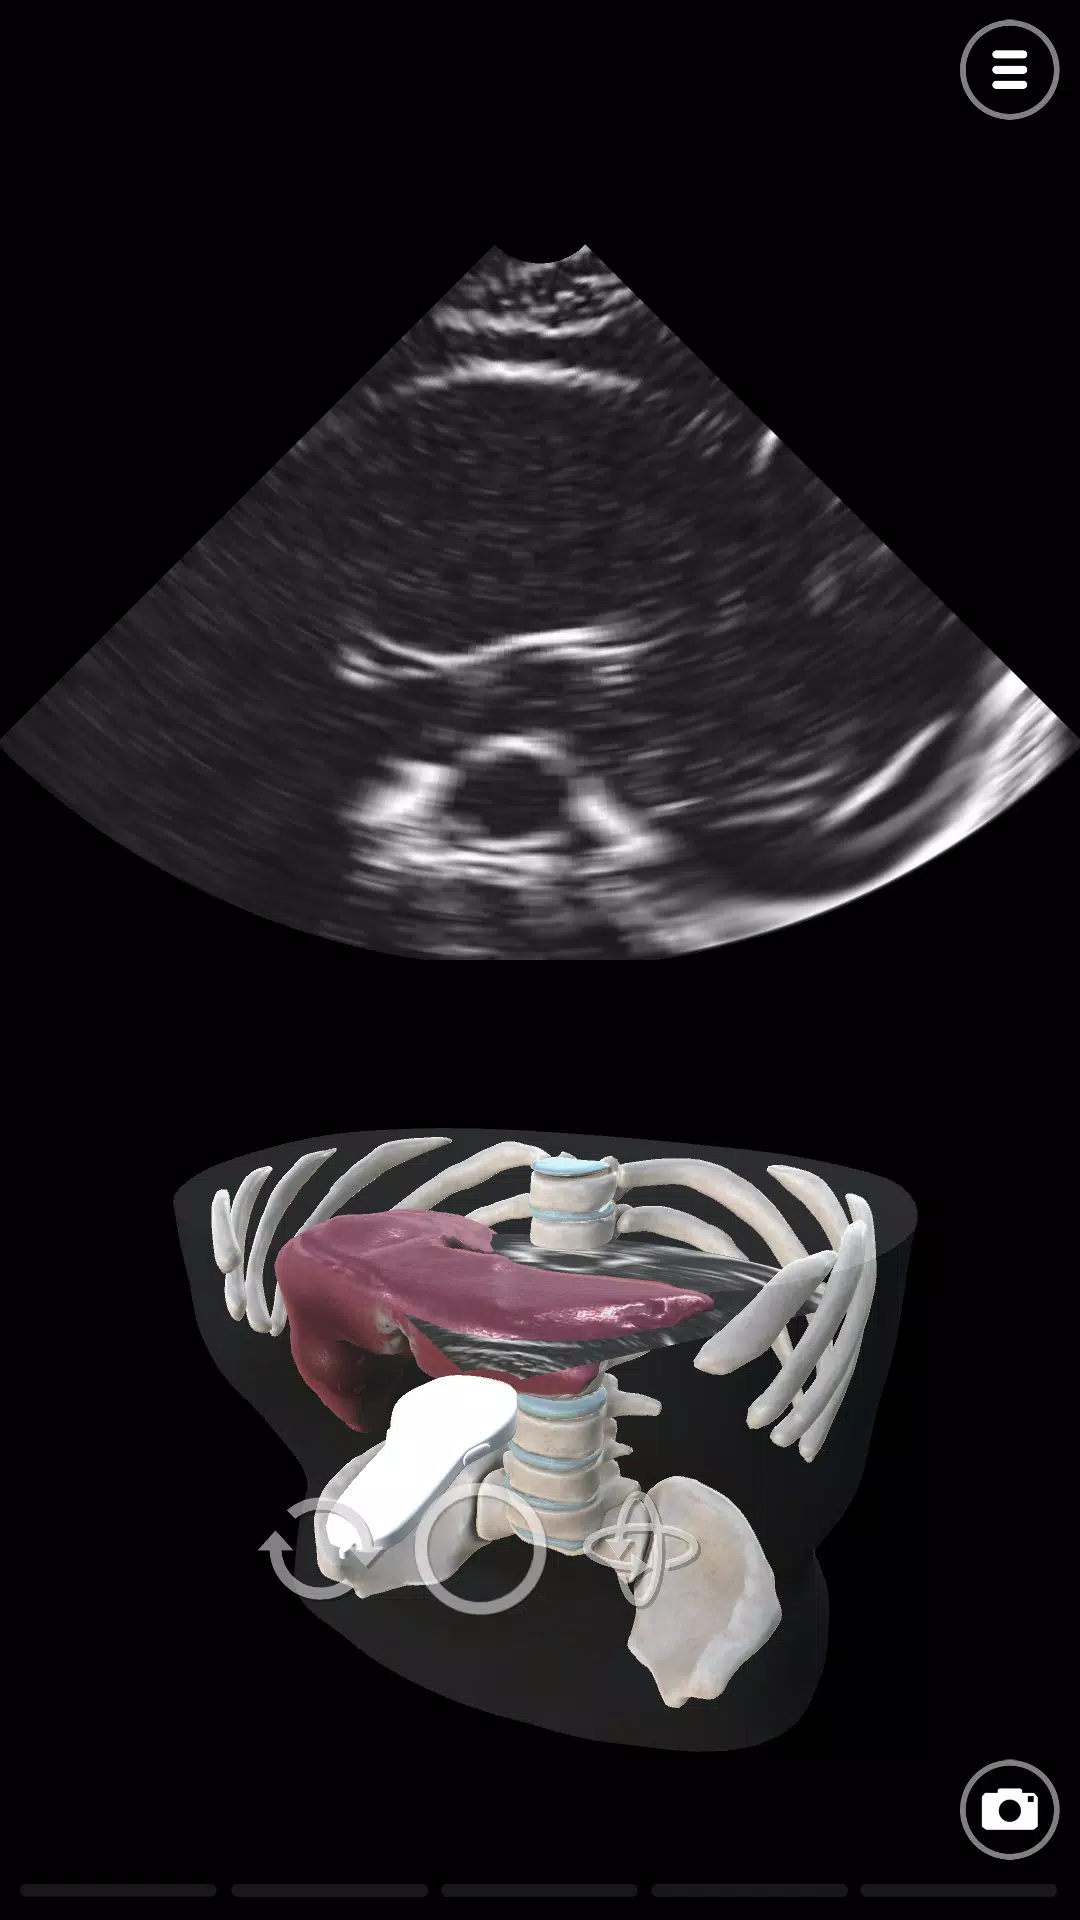

在超声模拟器中学习超声波或超声波扫描技术。 Deepscope超声学习模块由医生和超声医师创建。模块包括: - 基本超声或超声波探头运动 - 与超声扫描检查相关的解剖学 - 进行主动脉超声检查或超声检查的技术 - 进行超声心动图或回声的技术超声模拟器使用先进的计算机图形技术模拟声波。超声波图是作为这些模拟的结果而创建的。该应用程序旨在学习超声波检查或超声波。它可用于急诊医学(ER)超声,手术(术前)超声,骨科超声扫描,风湿病超声检查,血管超声检查,眼科超声和麻醉超声(麻醉学)。对于心脏病学,我们有超声心动图和回声模拟。Deepscope chāoshēng xuéxí mókuài yóu yīshēng hé chāoshēng yīshī chuàngjiàn.Mókuài bāokuò: - Jīběn chāoshēng huò chāoshēngbō tàntóu yùndòng - yǔ chāoshēng sǎomiáo jiǎnchá xiāngguān de jiěpōu xué - jìnxíng zhǔ dòngmài chāoshēng jiǎnchá huò chāoshēng jiǎnchá de jìshù - jìnxíng chāoshēng xīndòng tú huò huíshēng de jìshùchāoshēng mónǐ qì shǐyòng xiānjìn de jìsuànjī túxíng jìshù mónǐ shēngbō. Chāoshēngbō tú shì zuòwéi zhèxiē mónǐ de jiéguǒ ér chuàngjiàn de.Gāi yìngyòng chéngxù zhǐ zài xuéxí chāoshēngbō jiǎnchá huò chāoshēngbō. Tā kěyòng yú jízhěn yīxué (ER) chāoshēng, shǒushù (shù qián) chāoshēng, gǔkē chāoshēng sǎomiáo, fēngshī bìng chāoshēng jiǎnchá, xiěguǎn chāoshēng jiǎnchá, yǎnkē chāoshēng hé mázuì chāoshēng (mázuì xué). Duìyú xīnzàng bìng xué, wǒmen yǒu chāoshēng xīndòng tú hé huíshēng mónǐ. 最新版本2.0更新日志 Last updated on 2023年10月24日 New ModulesNew User Interface